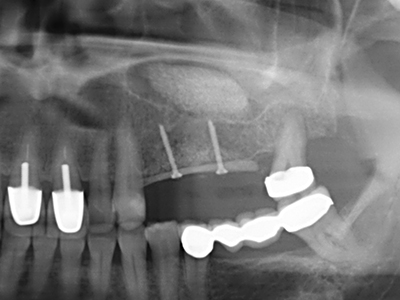

Si es preciso realizar intervenciones quirúrgicas en las que el hueso está en contacto directo con estructuras sensibles, como son los vasos sanguíneos o los nervios, los instrumentos rotativos presentan un enorme potencial de provocar lesiones iatrogénicas. Así, precisamente en la representación de nervios después de una lesión iatrogénica, o en el transcurso de la lateralización de un nervio para resecciones, reconstrucciones o incorporación de implantes, los equipos piezoeléctricos pueden resultar muy útiles para preparar la tapa ósea y retirar las partes de tejido duro cercanas al nervio (fig. 17-20). Por lo general, un ligero contacto del cordón nervioso con el inserto piezoeléctrico no tiene consecuencia alguna; ahora bien, un procedimiento poco cuidadoso con movimientos tipo sierra o piezas de trabajo sobre la base ósea aún existente puede provocar lesiones nerviosas temporales o incluso permanentes. Con todo, el riesgo de sufrir una lesión de este tipo se considera significativamente inferior que en los casos en los que se utilizan sierras y fresas (Pereira, Gealh et al. 2014).

Como ya se ha demostrado en el pasado, básicamente cualquier procedimiento de cirugía de hueso representa una posible indicación para la cirugía piezoeléctrica. Así, la preparación del segmento móvil en la osteogénesis de distracción (fig. 23-25) y en la osteotomía de sándwich puede realizarse con piezas especiales, sin poner en peligro el suministro sanguíneo de la parte crestal, que resulta esencial para el éxito de ambas técnicas (González-García, Diniz-Freitas et al. 2008).

Para la extracción de implantes es posible realizar la preparación de una tapa ósea vestibular que, tras retirar el tornillo del implante, vuelve a fijarse y, de este modo, mantiene el contorno de la apófisis alveolar.

En la cirugía del seno maxilar surgen otros campos de aplicación: En este punto, tras la preparación concéntrica de una tapa ósea de la pared del seno maxilar (que suele tener forma trapezoidal), es posible eliminar patologías y cuerpos extraños del seno maxilar. La tapa ósea se repone después de finalizar la parte intra-antral de la operación y se asegura frente a una posible dislocación mediante cuñas o suturas adaptables.